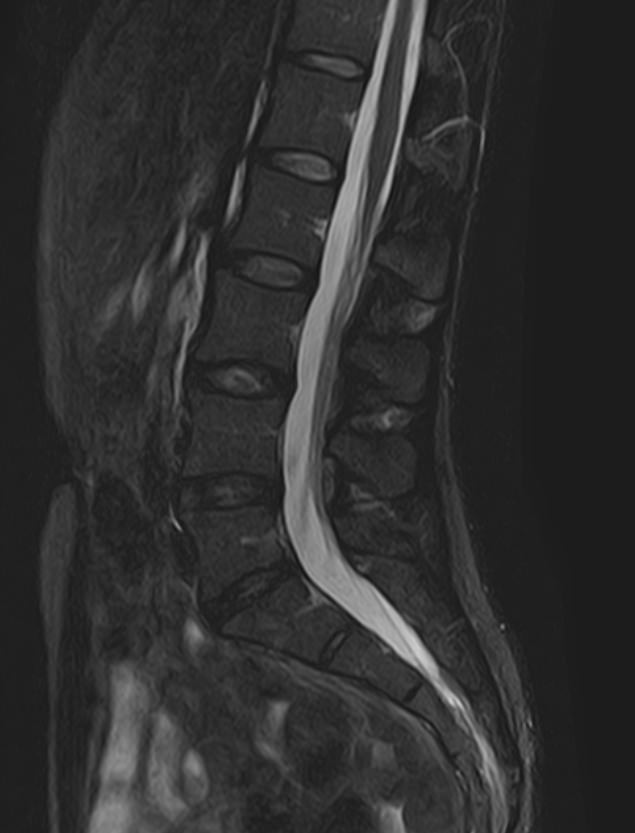

Боль в нижней части спины является наиболее распространенным симптомом различных заболеваний позвоночника, которые поражают пояснично-крестцовый отдел. В ряде случаев боли в нижних отделах спины сочетаются с кокцигодинией, то есть болями в рудиментарной части позвоночного столба – копчике. Причинами появления таких симптомов могут быть воспалительные процессы, дегенеративно-дистрофические заболевания позвоночника, опухолевые поражения данной анатомической области.

МРТ является наиболее информативным способом диагностики заболеваний позвоночника, так как позволяет оценить состояние костных структур позвонков, расположенную здесь часть спинного мозга с нервными корешками, а также связки, сухожилия и окружающие мягкие ткани. Магнитно-резонансная томография превосходит все другие методы диагностики не только по информативности, но и по безопасности, так как в основе метода лежит использование внешнего магнитного поля и отсутствует вредное для организма воздействие облучения, свойственное рентгену.

Для выявления причин появления кокцигодинии и болей в нижней части спины в клинике «Доступная медицина» проводится комплексное обследование МРТ пояснично-крестцового отдела + копчик, включающее два протокола исследования каждой анатомической области.